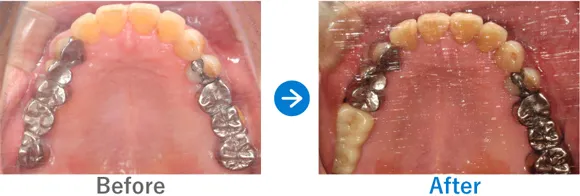

ほぼ虫歯な状態から、できるだけ歯を残した最小限のインプラントできれいな口元に

全顎ランパントカリエス(複数の歯に同時に虫歯が発生する状態)

インプラント4本:上顎2本、下顎2本、残せる歯はすべて補綴治療

4,917,000円(内訳:抜歯テルプラグ、GBR、根管治療、インプラント4本(ストローマン)、ガイド、全顎仮歯、補綴治療、セデーション、保証20年)

※当時の価格で現在とは異なる場合があります。

来院の背景

歯医者が苦手で、子供時代に歯科にかかったきりでした。ほとんどの歯に虫歯がある状態だったため、心配になったお父様が連れてこられました。

治療結果

まだお若いため、残せる歯はできるだけ残したうえで補綴治療(クラウンやブリッジなどによる治療)を行い、どうしても抜歯が必要な歯4本のみインプラントを行う方針で治療を進めました。

治療後は、見た目が整ったことはもちろん、しっかり噛めるようになったと喜んでいらっしゃいました。歯磨きが苦手とのことなので、定期メンテナンスでのアフターフォローも大切です。